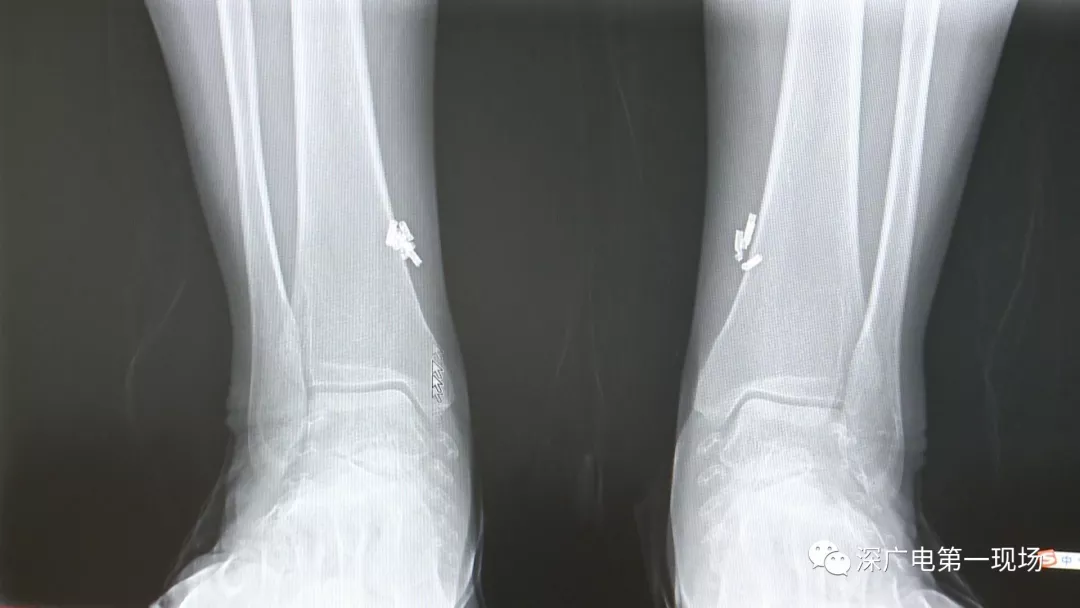

從X光影像圖片中可以看到

患者周身布滿了彈簧圈

深圳大學總醫(yī)院神經(jīng)外科副主任醫(yī)師陳富勇介紹,當時檢查的時候發(fā)現(xiàn),該患者從頭部到腿部,基本上每個地方都有彈簧,很難數(shù)清具體數(shù)目。